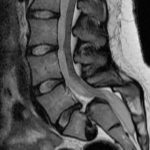

The intervertebral discs are the cushions or shock absorbers between the bones of the spine. As children and young adults, our discs contain a lot of water. As we age, disc nutrition becomes impaired, waste products build up within the disc and less water is contained within the disc.

Consequently the disc loses thickness and is less able to withstand the mechanical loads going through the spine. This is a normal ageing process but can lead to common problems such as back pain and ‘slipped discs’ with sciatica.

4. Spinal stenosis – this is narrowing of the bony canal or holes through which the nerves run. Often caused in older age by a combination of factors such as narrowing of the disc, enlargement of arthritic facet joints, bony spurs, etc.